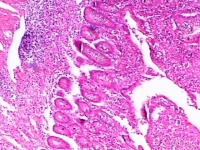

克罗恩病为贯穿肠壁各层的增殖性病变,并侵犯肠系膜和局部淋巴结。病变局限于小肠(主要为末端回肠)和结肠者各占30%,二者同时累及各占40%,常为回肠和右半结肠病变。Crohn将病理变化分为急性炎症期、溃疡形成期、狭窄期和痰管形成期(穿孔期)。本病的病变呈节段分布,与正常肠段相互间隔,界限清晰,呈跳跃区(skiparea)的特征。急性期以肠壁水肿炎变为主;慢性期肠壁增厚、僵硬,受累肠管外形呈管状,其上端肠管扩张。粘膜面典型病变有:①溃疡:早期浅小溃疡,后成纵行或横行的溃疡,深入肠壁的纵行溃疡即形成较为典型的裂沟,沿肠系膜侧分布。肠壁可有脓肿。②卵石状结节:由于粘膜下层水肿和细胞浸润形成的小岛突起,加上溃疡愈合后纤维化和疤痕的收缩,使粘膜表面似卵石状。③肉芽肿:无干酩样变,有别于结核病。肠内肉芽肿系炎症刺激的反应,并非克罗恩病独有;且20%~30%病例并无肉芽肿形成,故不宜称为肉芽肿性肠炎。④瘘管和脓肿:肠壁的裂沟实质上是贯穿性溃疡,使肠管与肠管、肠管与脏器或组织(如膀耽、阴道、肠系膜或腹膜后组织等)之间发生粘连和脓肿,并形成内瘘管。如病变穿透肠壁,经腹壁或肛门周围组织而通向体外,即形成外瘘管。